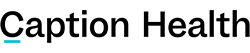

Caption Guidance™ uses artificial intelligence to empower medical professionals without specialized training to perform cardiac ultrasound.

BRISBANE, CA – February 7, 2020 – Caption Health, a leading medical AI company, announced today that the U.S. Food and Drug Administration (FDA) authorized marketing of Caption Guidance, software that assists medical professionals in the acquisition of cardiac ultrasound images. Caption Guidance uses artificial intelligence to provide real-time guidance and diagnostic quality assessment of images, empowering healthcare providers—even those without prior ultrasound experience—with the ability to capture diagnostic quality images. Empowering more clinicians with ultrasound image acquisition capability will bring the benefits of ultrasound to more patients, help standardize the quality of care, and help institutions realize valuable cost and time savings.

Caption Guidance was authorized via the De Novo pathway, a regulatory pathway reserved for novel technologies. The granting of this De Novo is groundbreaking, as Caption Guidance is the first medical software authorized by the FDA that provides real-time AI guidance for medical imaging acquisition. Caption Guidance is equipped with numerous features that together act as a co-pilot for clinicians when performing an ultrasound exam. The software emulates the guidance that an expert sonographer would provide to optimize the image, including providing real-time guidance on how to manipulate the transducer, and automated feedback on diagnostic image quality.

Marketing authorization was granted after the FDA reviewed extensive performance testing, including data from a pivotal multi-center prospective clinical trial conducted by Northwestern Medicine and Minneapolis Heart Institute at Allina Health, evaluating the use of Caption Guidance by registered nurses (RNs) with no prior ultrasound experience. Caption Guidance successfully met its primary endpoints, meeting the pre-specified criteria for study success.

In this study, eight RNs with no prior ultrasound experience used Caption Guidance to perform ultrasound exams on 240 patients, following a short training course. Patients were stratified to include a wide range of body-mass index and cardiac pathologies. The RNs acquired limited echo exams of 10 views each. Each exam was assessed by a panel of 5 expert cardiologists to determine if the exam was of sufficient quality to make a set of specific qualitative visual assessments.

Caption Guidance successfully met all four primary endpoints, meeting the pre-specified criteria for study success by acquiring images of sufficient quality for specific clinical assessments. Namely, the RNs successfully acquired limited echo exams for qualitative visual assessments of left ventricular size: 98.8%, 95% CI [96.7, 100]; left ventricular function: 98.8% [96.7, 100]; right ventricular size: 92.5% [88.1, 96.9]; and pericardial effusion: 98.8% [96.7, 100].